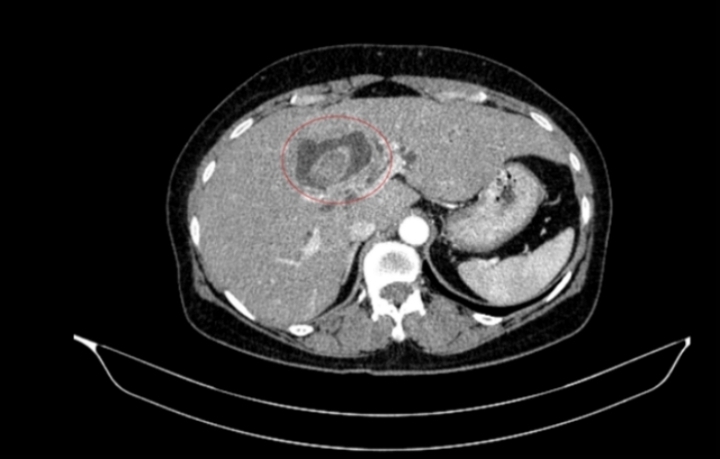

Một phụ nữ 59 tuổi được các bác sĩ Trung tâm Y học hạt nhân và Ung bướu, Bệnh viện Bạch Mai, tiếp nhận trong tình trạng vàng da, ngứa và đau vùng hạ sườn phải kéo dài. Kết quả chẩn đoán hình ảnh ban đầu ghi nhận tổn thương đường mật trong gan kèm sỏi và giãn đường mật.

Sau hội chẩn đa chuyên khoa, các bác sĩ xác định bệnh nhân mắc đồng thời hai ung thư nguyên phát, thay vì một khối u di căn. Cụ thể, ung thư đại tràng phải ở giai đoạn sớm, chưa di căn hạch, trong khi ung thư đường mật trong gan đã ở giai đoạn tiến triển, có xâm lấn và di căn hạch.